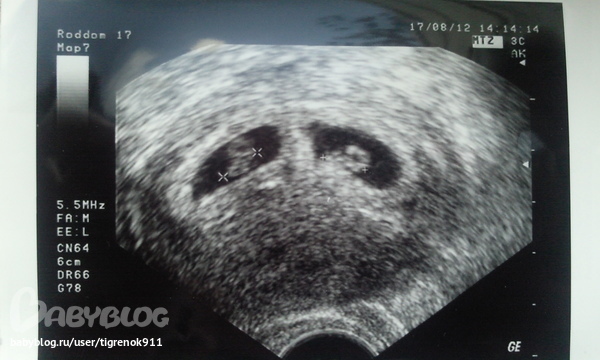

И фоточки мои красотуль!

6-7 недель: